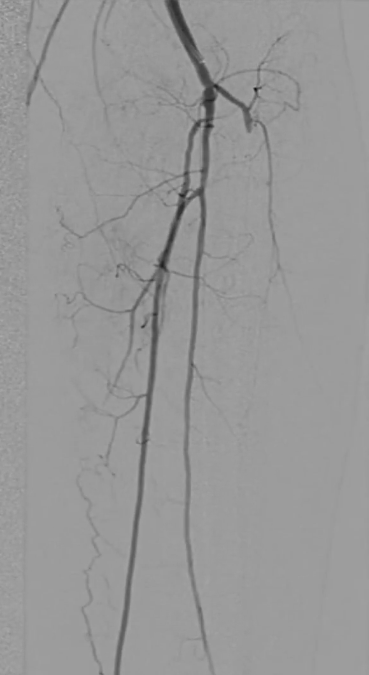

调整与确认:开通至股浅动脉中段后,发现导丝向另一个方向打弯,退回后重新选择路径,最终顺利送至股浅动脉远端真腔,造影证实开通成功。

考虑到超声导管的使用以及导丝通过时顺滑度,认为病变大部分是真腔通过,因此考虑对股浅动脉减容处理。

预扩张:先用3mm球囊对病变段预扩张,便于后续器械导入。